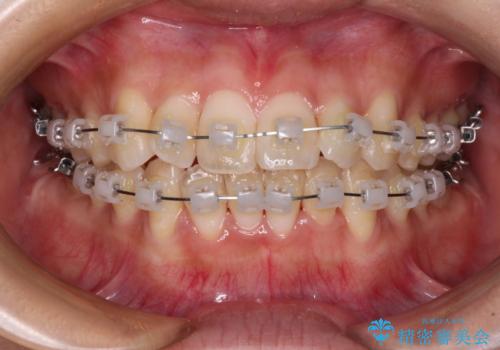

- クリアブラケット

- 1年6ヶ月

- 10-30回

日々前歯の捻れが解消されていくので、歯の動きを楽しみながら矯正治療を進めることができました。